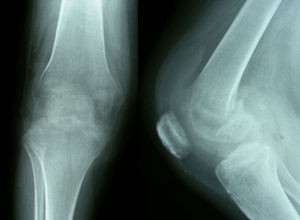

Pruebas complementarias. El estudio radiológico inicial mostró una radiolucencia difusa de la metáfisis y la epífisis femoral distal, sin líneas de fractura; el espacio articular permanecía normal (fig. 1). La resonancia magnética (RM) mostraba un extenso edema óseo en la epífisis femoral distal, más marcado en cóndilo externo, con disminución de la señal en T1 y aumento en T2, además de un pequeño derrame articular difuso (fig. 2).